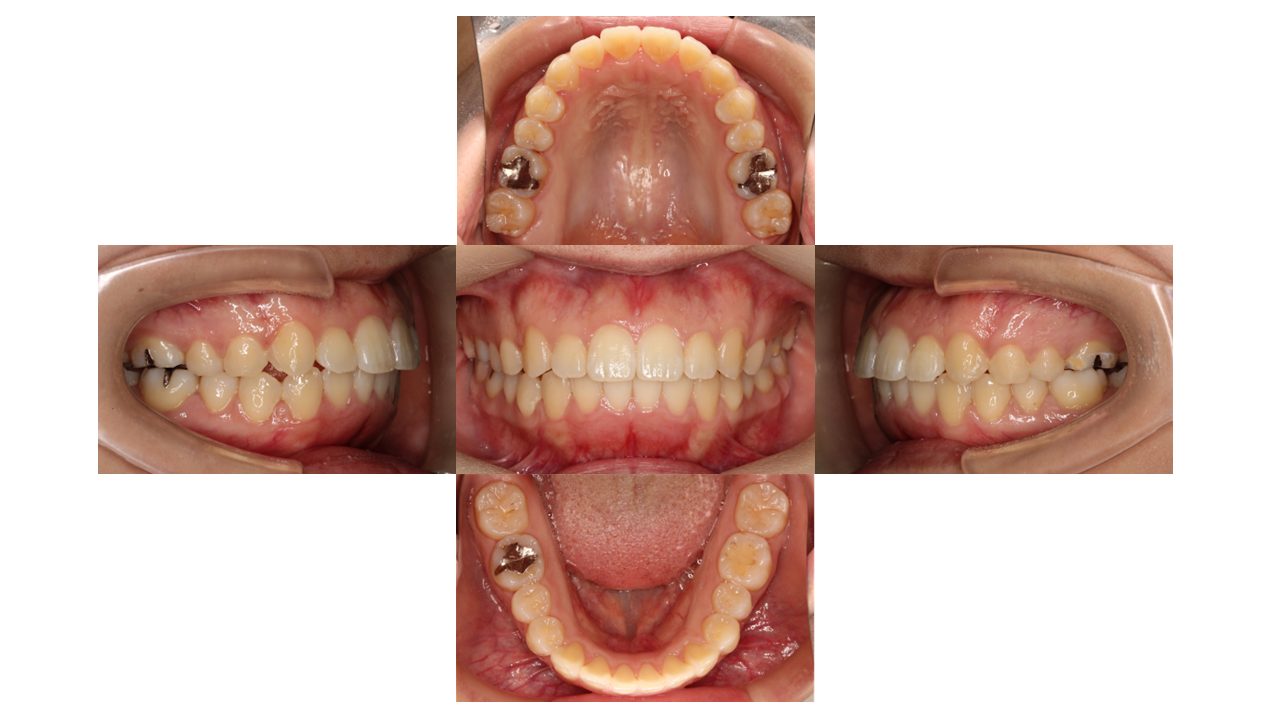

2年9か月経過の口腔内の状態です。

前歯の凸凹・八重歯が改善されたとご満足いただけました。

| 治療費用 | 検査・診断:税込38,500円/マウスピース矯正(インビザライン):税込990.000円 |

| 治療期間 | 2年9か月(19回) |

| 抜歯 | 無(非抜歯) |

| 矯正の装置 | マウスピース矯正(インビザライン) |

| 副作用、リスク | 歯肉退縮,歯根吸収,疼痛,咬合の違和感,装置の違和感,虫歯,歯肉炎 |